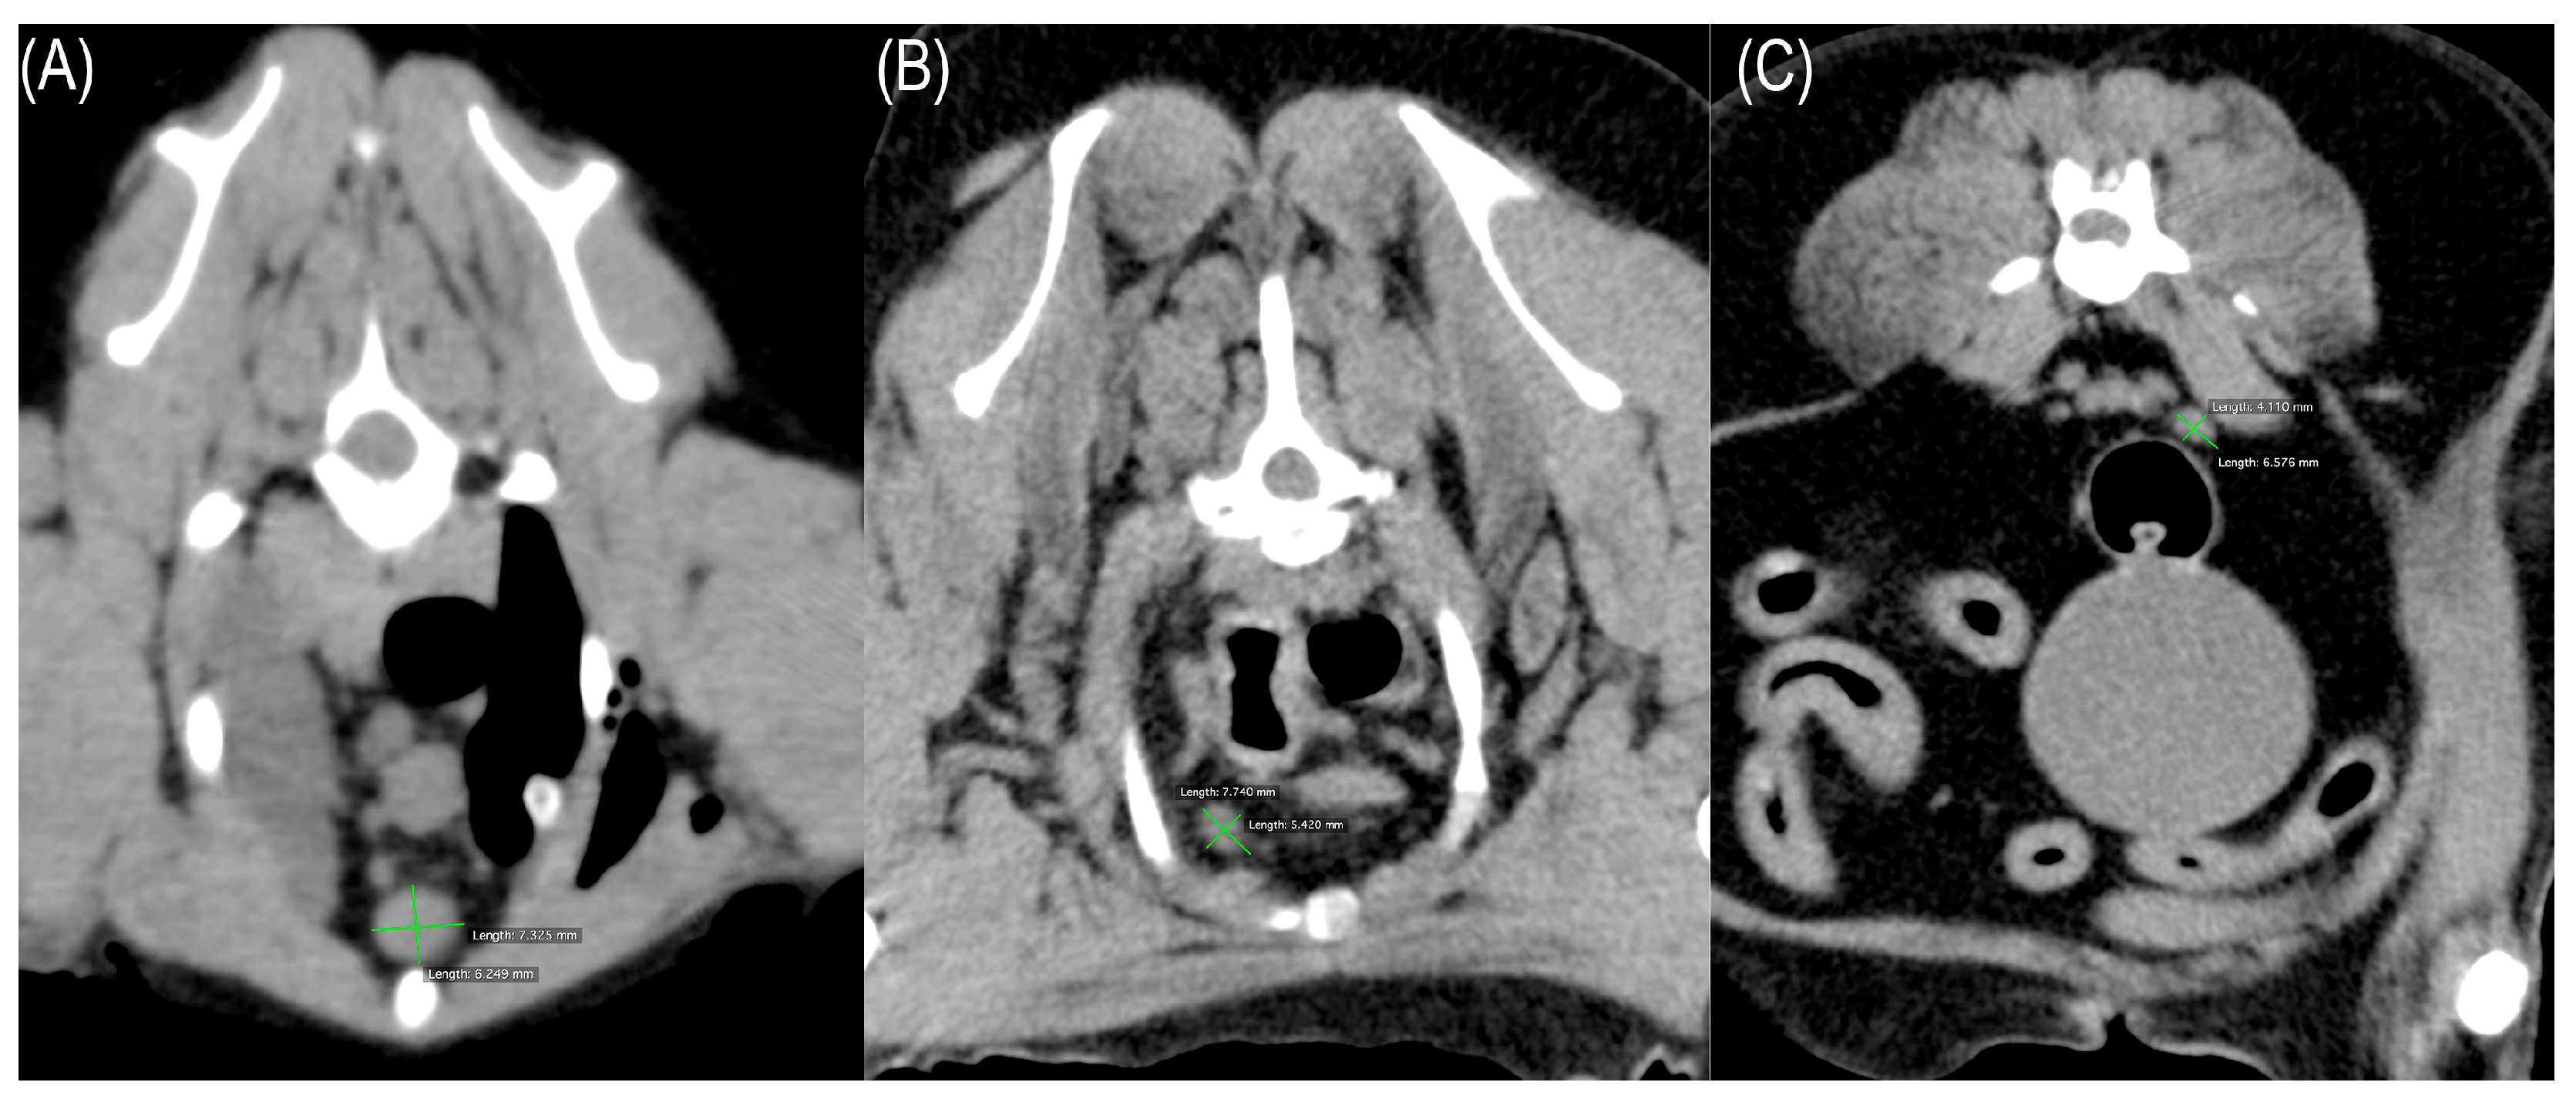

2.2. Evaluation of Lymph Node Images

| Sternal lymph nodes | |

| No. measurable | n = 68 |

| Mean diameter | 4.4 mm (max–min: 8.3–2 95%CI: 4.7–4.0) |

| Clinically enlarged | 4 (>7 mm) |

| Cranial mediastinal lymph nodes | |

| No. measurable | n = 69 |

| Mean diameter | 4.5 mm (max–min: 9.3–2 95%CI: 4.9–4.1) |

| Clinically enlarged | 9 (>6 mm) |

| Internal iliac lymph nodes | |

| No. measurable | n = 73 |

| Mean diameter | 4.8 mm (max–min: 8.1–2.1 95%CI:5.1–4.5) |

| Clinically enlarged | 15 (>6 mm) |